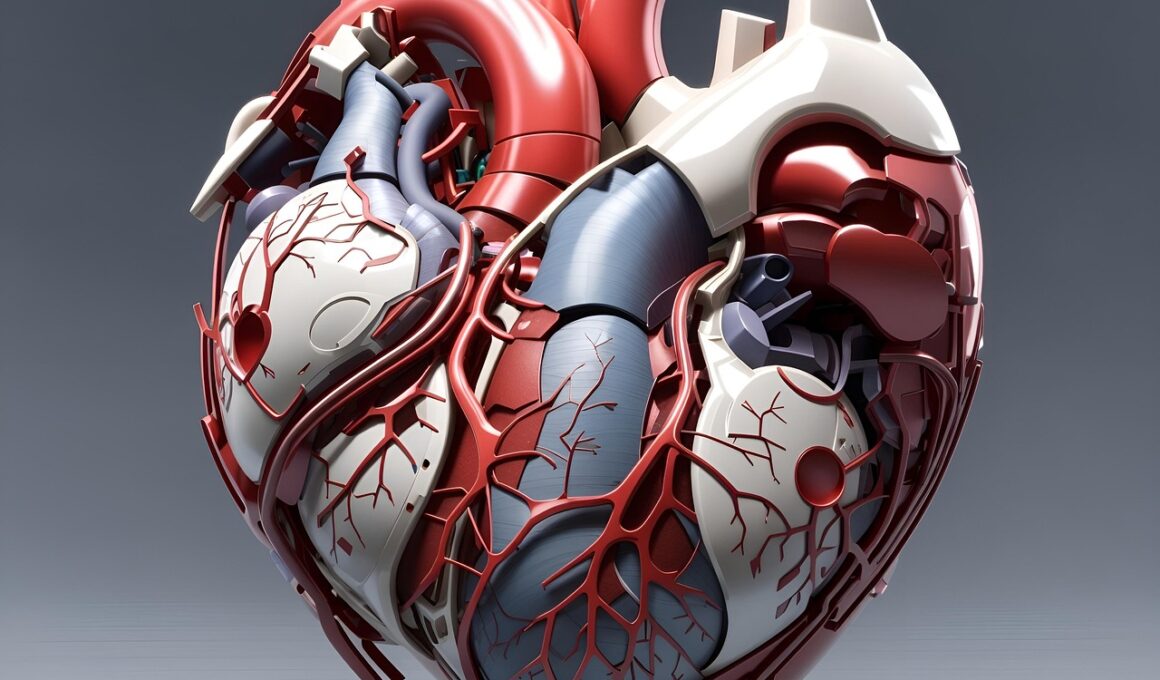

Hormone Replacement Therapy (HRT) is a significant medical treatment often prescribed to alleviate symptoms associated with hormonal imbalances. Particularly in women experiencing menopause, HRT aims to restore balance by supplementing estrogen, progesterone, and testosterone levels. Recent studies indicate that this therapy can influence cardiovascular health positively. By reducing symptoms such as hot flashes and mood swings, patients may find it easier to engage in regular exercise. Furthermore, HRT may aid in improving lipid profiles, which can reduce the risk of cardiovascular diseases. Yet, the impact varies among individuals, making a personalized approach essential for optimal results. Notably, HRT’s role in exercise capacity growth and overall health enhancement is gaining attention, but thorough research remains vital. Consulting healthcare providers for tailored treatment plans is critical, considering potential benefits and risks. Overall, integrating HRT with a healthy lifestyle can significantly influence physical well-being and cardiovascular resilience.

Moreover, the practice of Hormone Replacement Therapy has broadened potential avenues for improving cardiovascular wellness. Patients often express concerns about their heart health, particularly during hormone fluctuations that can influence weight and metabolism. HRT can help regulate these hormonal fluctuations, thereby supporting metabolic functions. Clinical studies indicate that women utilizing HRT experience reduced risks of developing coronary artery disease. Furthermore, HRT aids in regulating blood pressure and improving arterial health, creating a healthier cardiovascular environment. This improvement is essential for individuals regularly engaging in physical activity, as effective circulation enhances oxygen delivery to tissues during exercise. Understanding the intricate relationship between hormones and cardiovascular function can motivate patients to adopt exercise routines tailored to their improved well-being. Maintaining open communication with healthcare professionals is crucial to assess any adjustments needed in treatment plans when incorporating exercise. Ideally, personalized programs should include guidelines for physical activity while undergoing HRT. This approach emphasizes a well-rounded strategy focusing on both hormonal balance and exercise-driven cardiovascular health.